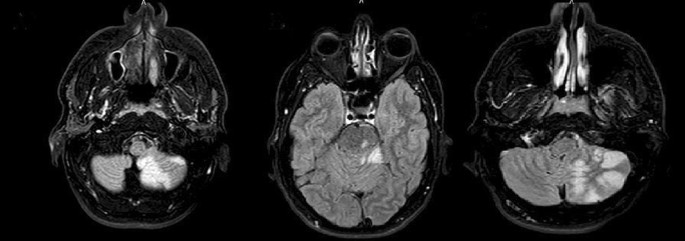

Chest radiograph, echocardiogram of the heart, and chest computerized tomography (CT scan) were normal. Moreover, the initial cerebral angiography and electroencephalography were also normal. Brain magnetic resonance imaging (MRI) showed cerebral vasculopathy with possible stroke and inflammation of the arteries associated with COVID-19 (Fig. 1). MRI with Gd injection had no enhancing lesion. The patient received supportive cares and was treated with routine antiplatelet therapy. Finally, the patient did not present post-operative neurological complication and his symptoms improved completely and discharged 10 days after admission with no symptoms.

Vascular impairment in posterior cerebral circulation